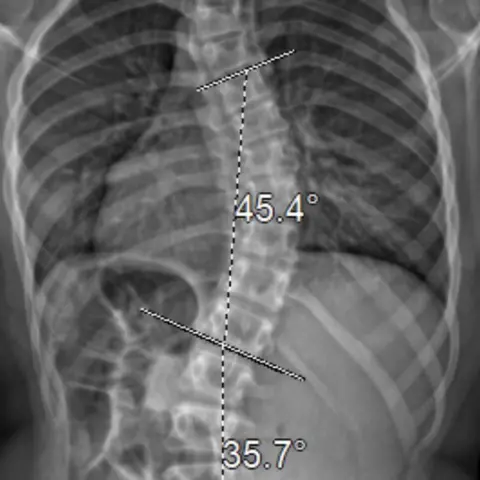

Hellen familyAn 11-year-old girl has been unable to fly to the US for spinal surgery to help correct her "painful" scoliosis due to coronavirus.

The specific technique, known as "vertebral body tethering", is not currently available on the NHS.